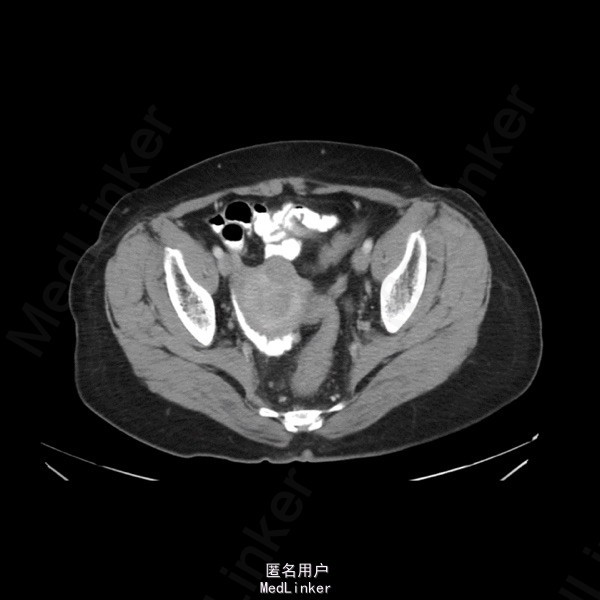

治疗前肠镜:1、直肠癌(距肛门缘约为6-14cm),病变合并出血,建议对症治疗。2、结肠多发息肉,必要时择期内镜下切除。病理:(直肠)腺癌,(升结肠、横结肠)管状腺瘤 直肠超声:直肠癌,病变主要位于肠壁的固有肌层,病变侵及直肠壁周围脂肪组织。 腹盆CT :1、直肠、乙状结肠移行处癌,侵透纤维膜,伴周围转移。2、左侧髂总、髂内、右侧髂内外血管间及骶前多发淋巴结,警惕转移可能,请追随。3、子宫肌瘤。 钡灌肠:直肠上段,有一长约6cm不规则充盈缺损、粘膜破坏,管腔狭窄,与周围正常肠管分界清楚,余段肠管未见明确异常 直肠MR:肠壁环周性增厚,最厚处约2.6cm,范围长约4.8cm,周围可见多发淋巴结,大者约1.4*0.8cm。 “直肠癌放化疗后”,对比上次腹盆CT:1、直肠皱缩,直肠上段管壁增厚,纤维膜面毛糙,较前缩小,请结合造影和镜检。2、左侧髂总、髂内、右侧髂内外血管间及骶前多发淋巴结,较前缩小,现大者短径约0.6cm。3、余腹膜后、腹腔内未见明显肿大淋巴结。未见腹水。